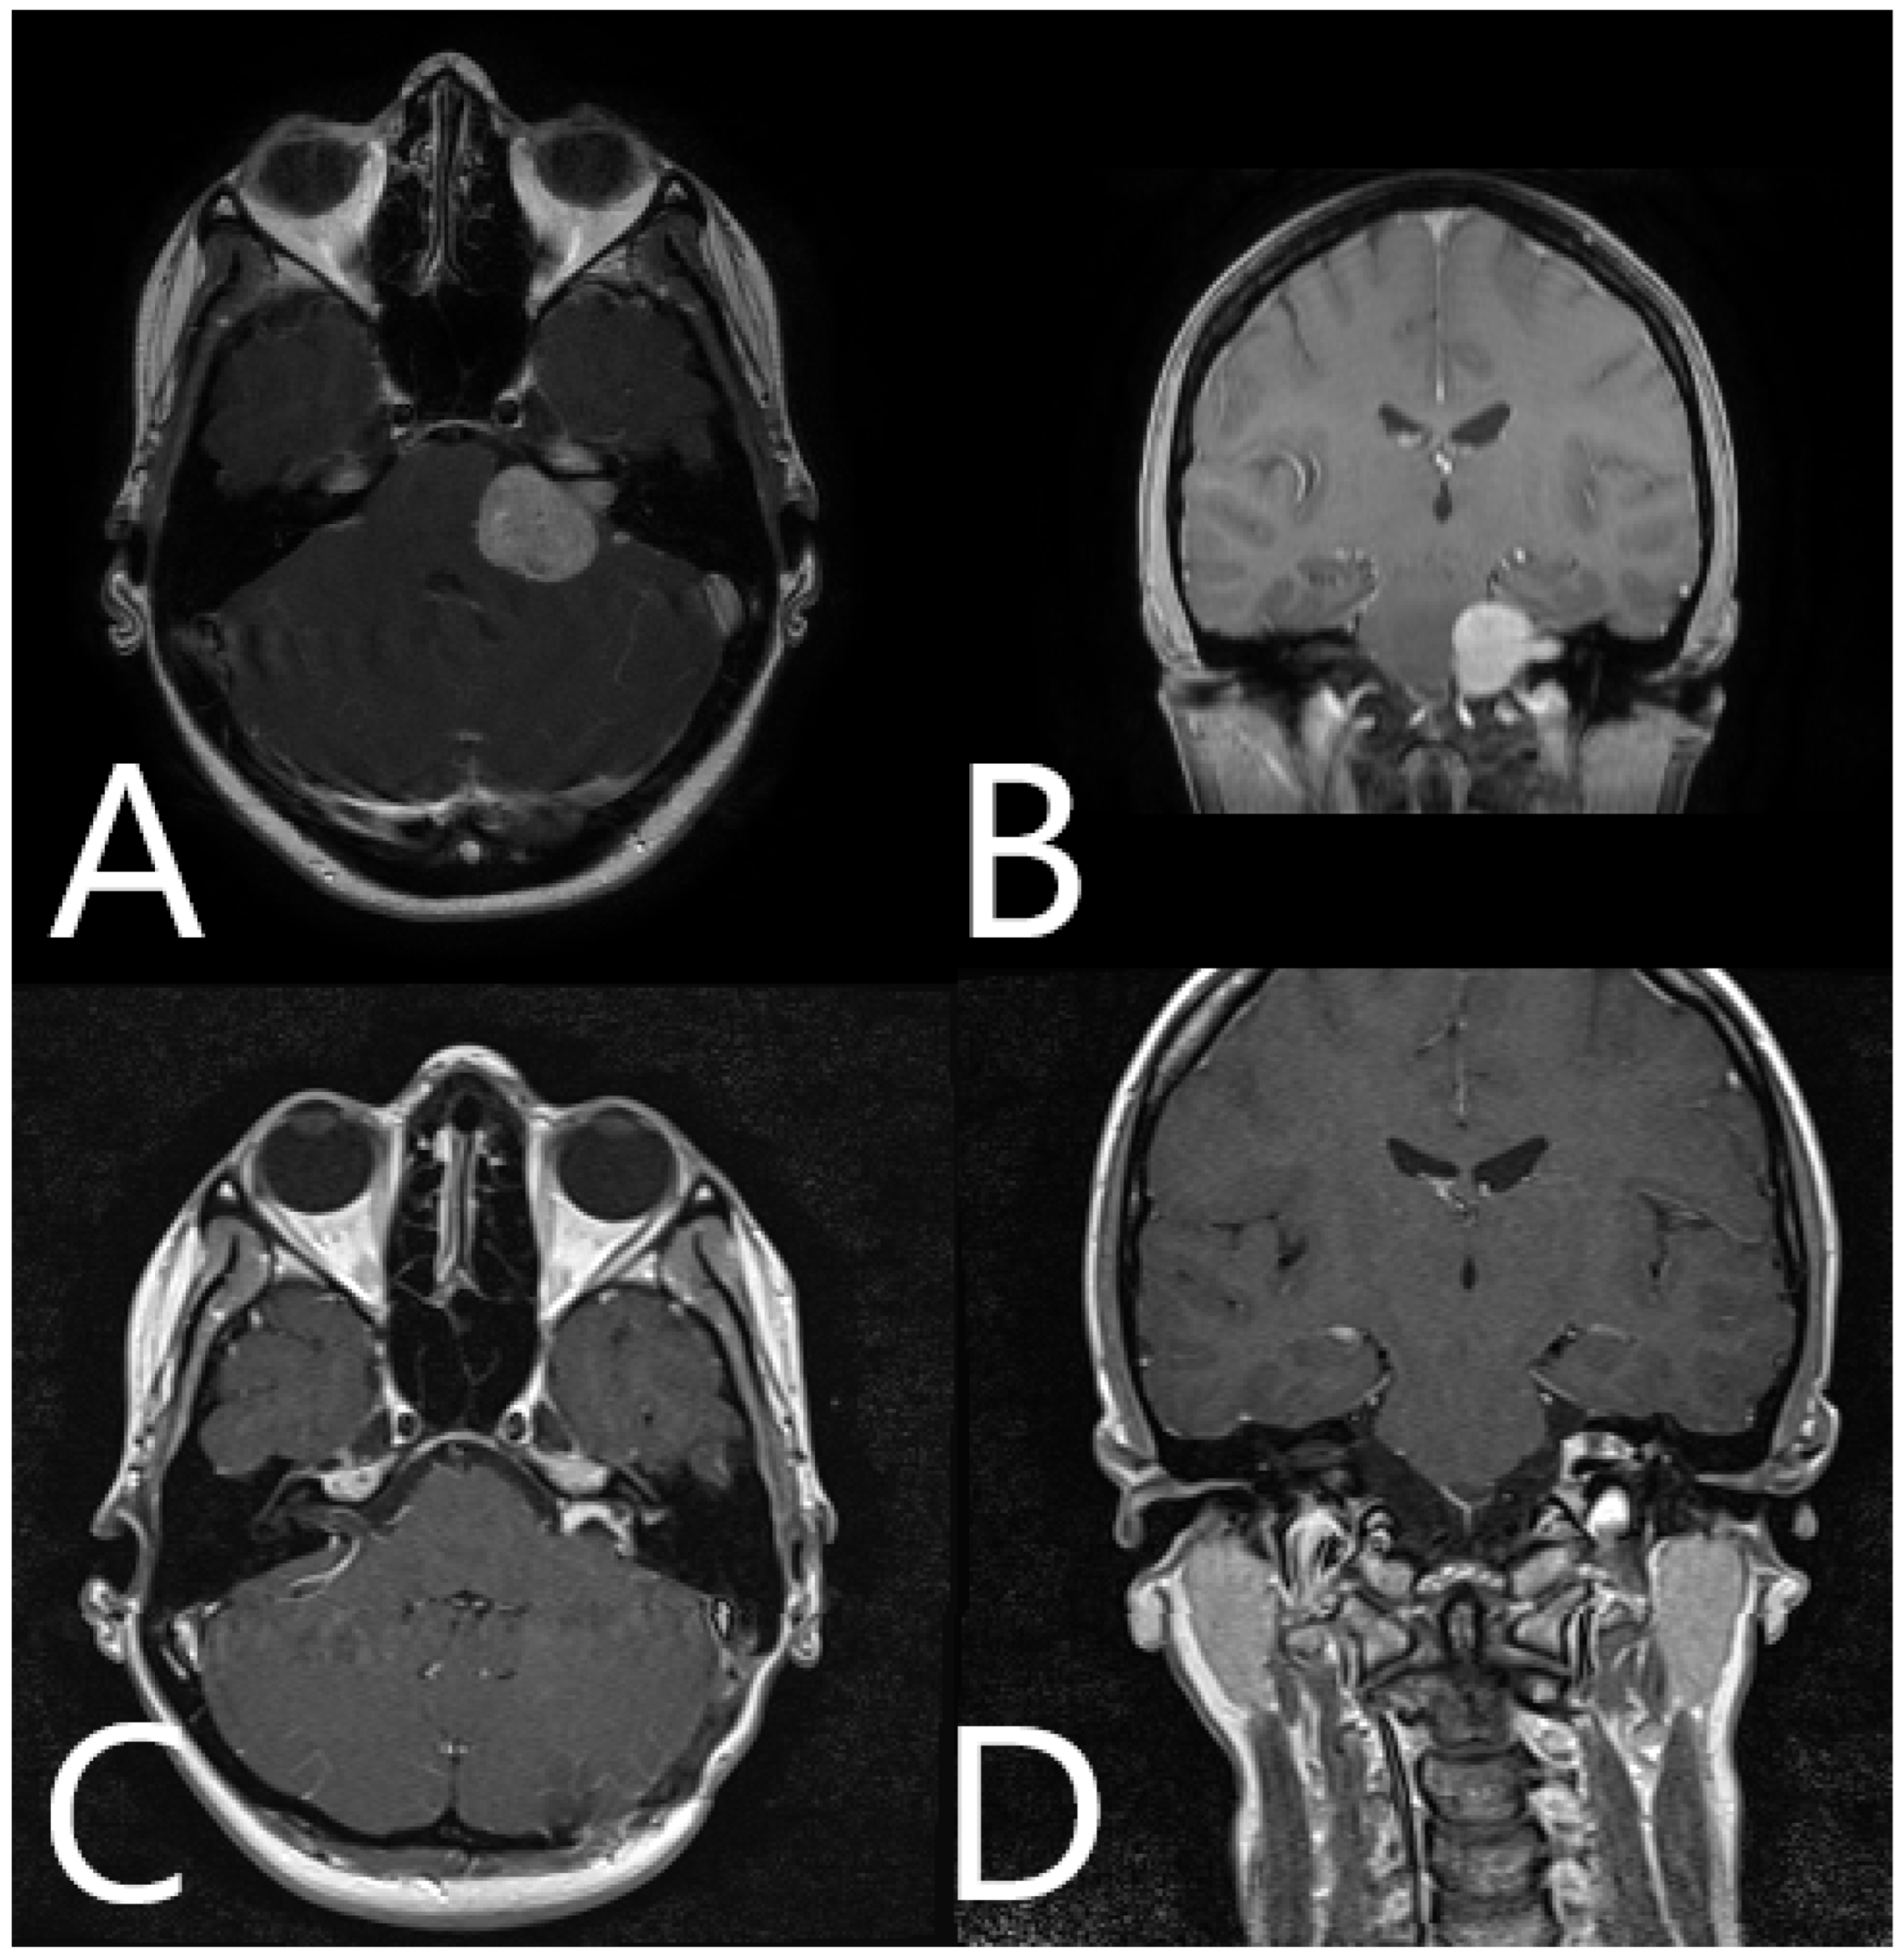

Illustrative Cases